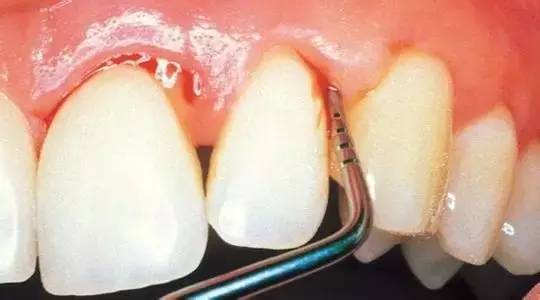

第四步急性牙髓炎。

当您昨晚一夜未眠,牙齿疼得撞墙时,您强忍着说:“吃一颗止痛药吧,再忍忍。”牙医劝您说:“当病变侵入牙髓组织,产生炎性渗出液,因而形成髓腔高压,引起剧烈疼痛。此时,开髓引流是缓解急性牙髓炎疼痛最有效的方法。”